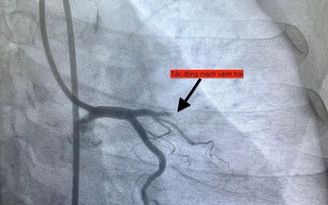

Trường hợp thứ nhất, lúc 0 giờ 34 phút ngày 14.11, nam bệnh nhân 51 tuổi vào bệnh viện vì mệt và khó thở. Chụp mạch vành phát hiện bệnh nhân bị tắc hoàn toàn động mạch vành phải.

Hình ảnh chụp mạch vành cho thấy các bệnh nhân bị tắc mạch máu tim (do mảng xơ vữa, huyết khối) dẫn đến tình trạng thiếu máu cục bộ và nhồi máu cơ tim cấp

ẢNH: BV